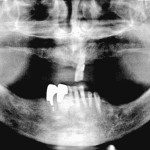

Osteonecrosi da bifosfonati della mandibola con disodontiasi del 3.8

Riassunto

I bifosfonati sono una classe di farmaci derivati da analoghi strutturali del pirofosfato inorganico e hanno la funzione di regolatori endogeni della mineralizzazione ossea....